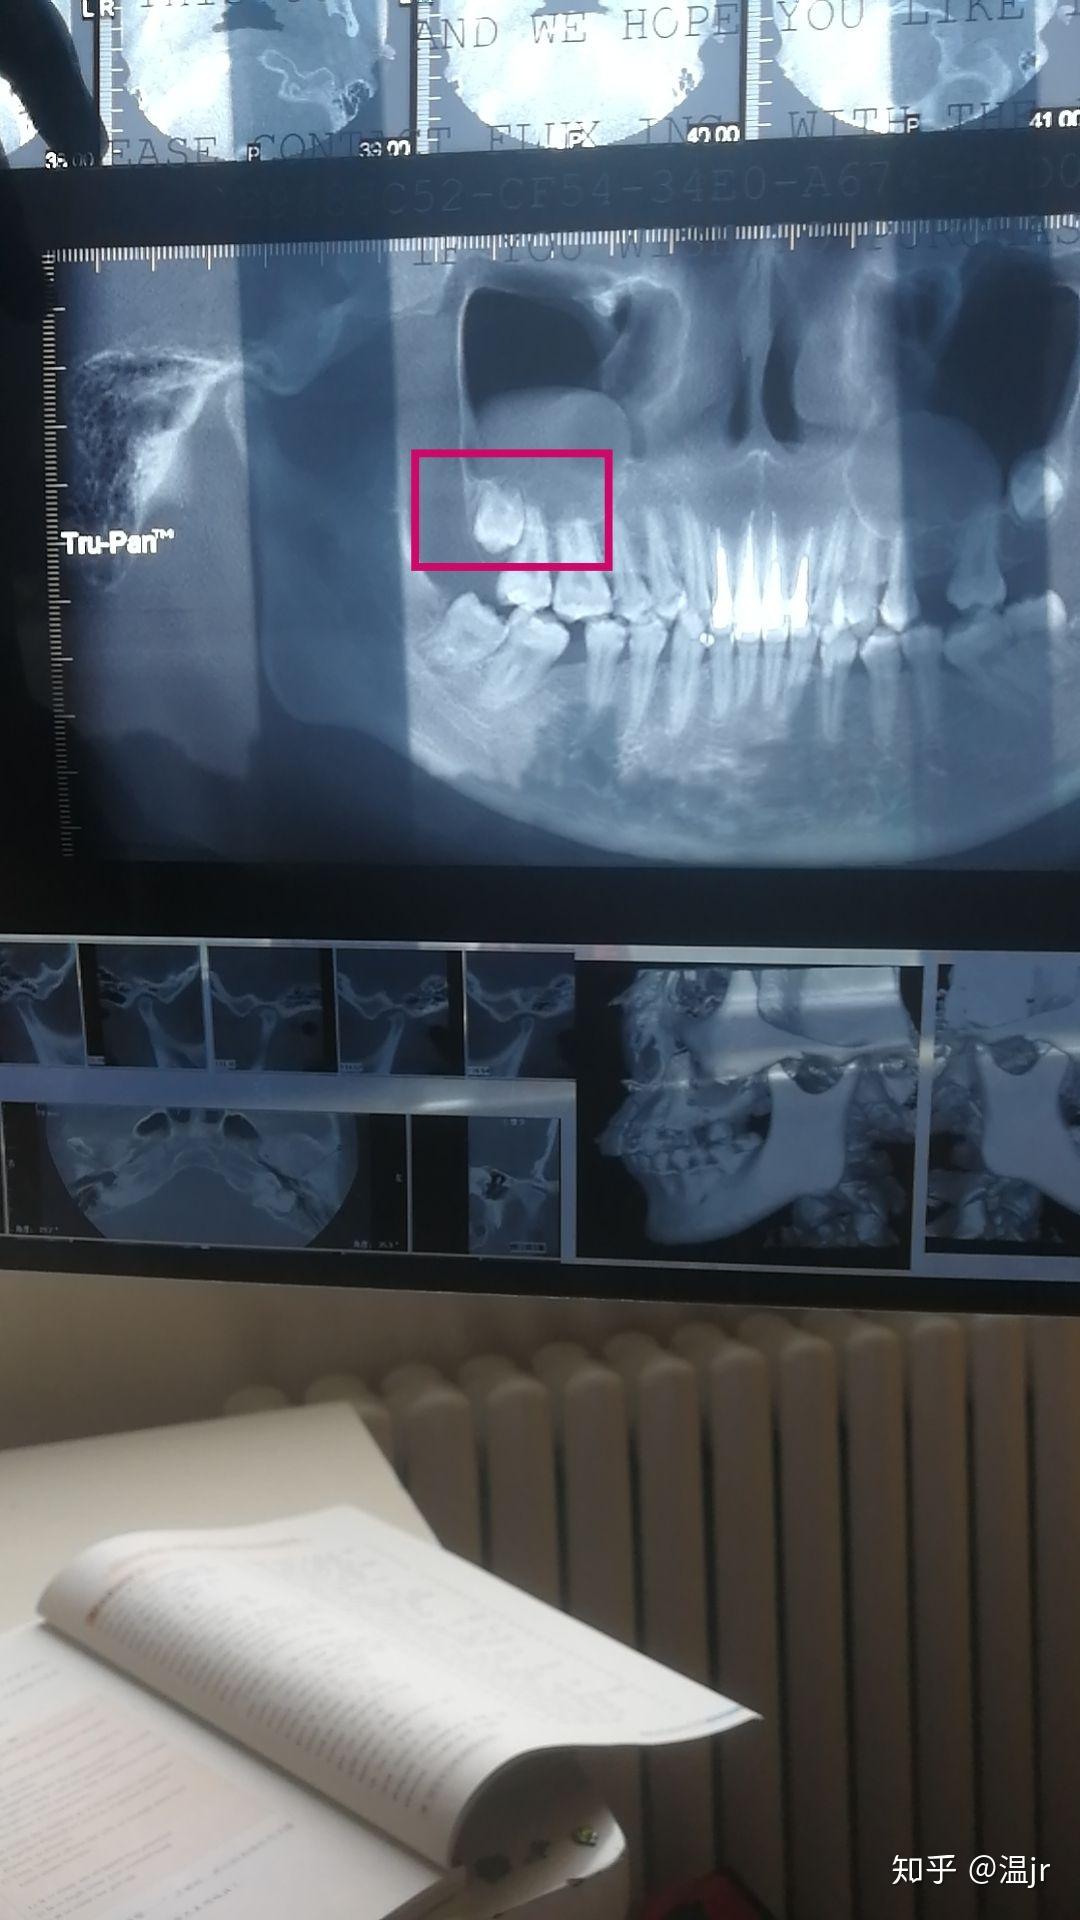

拔智齿,连通上颌窦严重吗? - 知乎

图片尺寸1080x1920